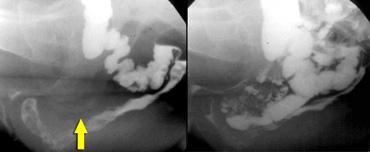

TRÁI: Nghi ngờ bệnh lý do khoảng cách lớn giữa trực tràng và âm đạo. Bệnh nhân chưa được uống thuốc cản quang. PHẢI: Sau khi uống thuốc cản quang barium dạng lỏng, quan sát thấy một thoát vị ruột non vào túi cùng Douglas (enterocele) kích thước lớn.

Hai giờ trước khi thực hiện thủ thuật, bệnh nhân uống 135 ml thuốc cản quang barium dạng lỏng để làm hiện ảnh ruột non (hình).